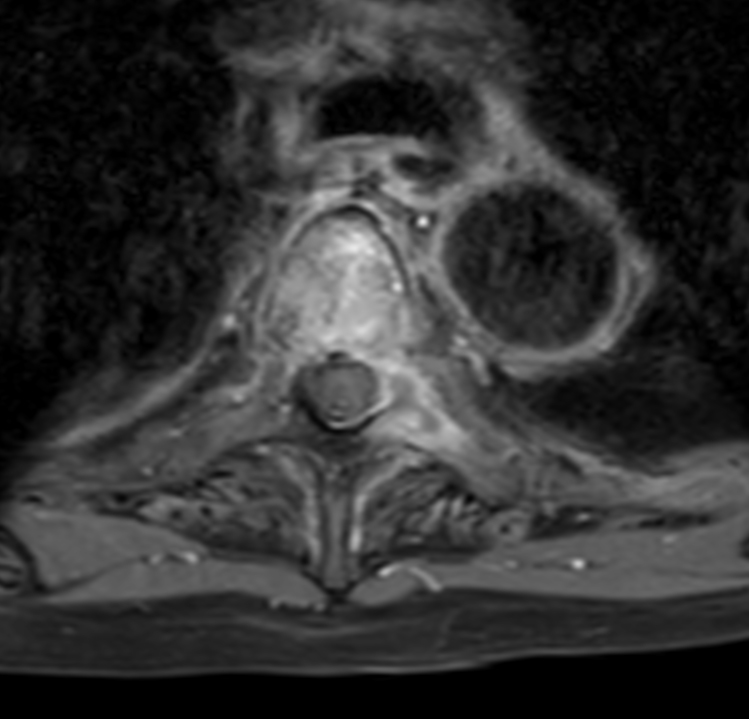

Axial T1w mDIXON XD TSE (In Phase) +gado (T4)